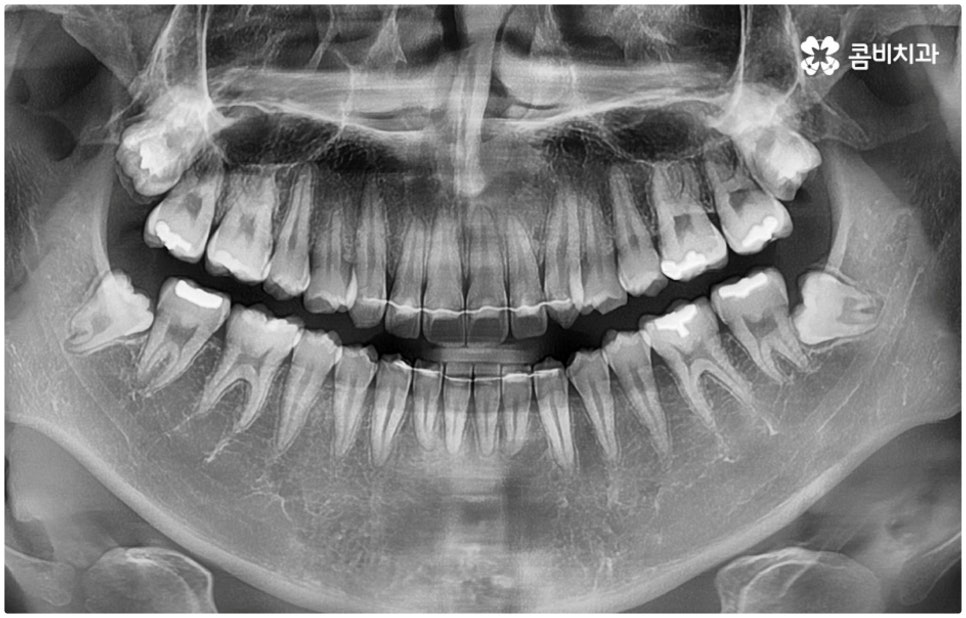

우리가 흔히 사랑니라고 부르는 치아의 정식 명칭은 제3대구치로 세 번째로 큰 어금니라는 뜻을 가지고 있습니다. 보통 10대 후반에서 20대 초반 사이, 즉 사랑을 알게 되는 나이에 나온다고 해서 사랑니라는 별명이 붙었지만 사실 개인마다 나오는 시기, 형태 등에 차이가 크기 때문에 언제 맹출이 된다고 확실하게 말할 수 없으며, 통증이나 붓기 등 관련 증상도 굉장히 다양한 편이라고 할 수 있어요. 또한 사랑니의 개수도 상하좌우 4개 모두 있는 사람도 있고 1~3개 있는 사람도 있으며 현대에 들어 유전적으로 턱뼈가 점점 작아짐에 따라 아예 사랑니가 없는 케이스도 존재하기 때문에 각자의 사랑니 유형에 대해서 자세하게 알기 위해서는 18세 전후 즈음해서 정밀 검진을 해 볼 필요가 있습니다.

사랑니라고 해서 반드시 뽑아야 하는지 문의를 주시는 분들이 많은데 똑바로 나오고 위생 관리를 청결하게 할 수 있다면 꼭 발치를 해야 하는 것은 아니지만 사랑니 자체에 문제가 생겼거나 주변 치아에 좋지 않은 영향을 준다면 뽑아주는 것이 좋을 거예요. 말씀드린 것처럼 사랑니는 다른 치아가 모두 나오고 나서 가장 늦게 맹출이 되기 때문에 사랑니가 자랄 만한 공간이 부족하여 대부분 삐뚤어져 나오거나 일부만 나오는 등 정상적인 치열을 벗어나는 경우가 많으며, 위치상 구강 내 최후방에서 나오기 때문에 그렇지 않아도 관리가 어려운 상황에서 잘못 나온 사랑니로 인해 비좁은 틈이 생겨 속속들이 낀 음식물 찌꺼기가 빠지기 어렵게 되면 충치 또는 잇몸 염증이 생기기 쉽고 이로 인해 심한 구취를 유발하거나 주변 어금니까지 손상될 가능성이 높아지므로 주의하실 필요가 있어요.

대부분 이와 같이 사랑니가 날 때 잘못 나오기 때문에 붓고 아프고 그쪽으로 씹기 불편해 지는 등 여러 증상이 동반되므로 발치 처치를 받고자 치과에 내원하시는 분들이 많긴 하지만 경우에 따라 전혀 맹출이 되지 않거나 별다른 증상 역시 드러나지 않음에도 불구하고 발치가 필요한 케이스가 있을 수 있으므로 통상적으로 사랑니가 나온다고 알려진 시기 즈음 해서 치과에 내원하여 꼼꼼하게 정밀 검진을 받아보시길 권유드리고 있습니다.

특히 매복 사랑니 중 잇몸 속에 전부 묻혀 있는 사랑니를 완전매복사랑니라고 부르는데 이 경우 누운 방향으로 자라나면서 앞 어금니 뿌리에 지속적인 압박을 가하여 신경을 누르기도 하고 치근을 흡수시키거나 치열이 앞쪽으로 쓰러지게 만들어 부정교합을 유발하기도 하며 드물게는 함치성 낭종이 생겨 턱뼈를 녹이는 상황까지 발생할 수도 있기 때문에 꼼꼼하게 검진을 하여 만약에 필요하다면 늦지 않게 발치 처치를 해 주어야 하는 거예요.